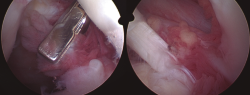

Todos los casos de hombro fueron tratados de manera artroscópica, y los hallazgos incluyeron la presencia de vellosidades características del LA (Figura 3), así como roturas en el seno del manguito rotador. Esta sinovitis proliferativa de aspecto graso se ubicaba predominantemente en la zona del intervalo rotador y en la periferia de la glena e inserción del tendón de la porción larga del bíceps.

Figura 3. Imágenes artroscópicas de las vellosidades del LA en el hombro, así como los cambios artrósicos en la articulación glenohumeral.